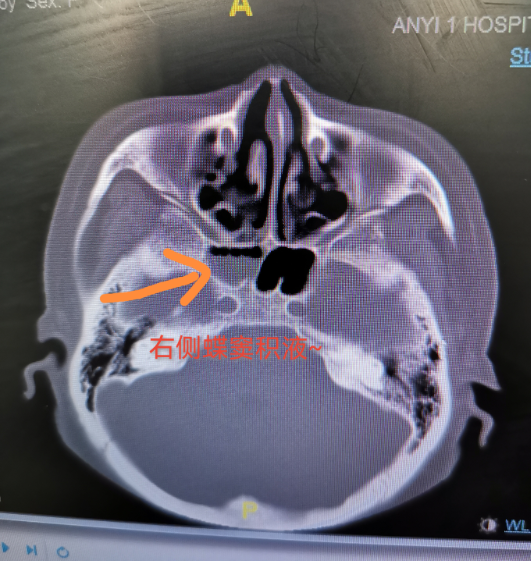

通过鼻内镜检查,医生发现,王大妈用力咳嗽时,鼻腔里的水样鼻涕会突然增多,觉得可能是“脑脊液鼻漏”。进一步检查证实:王大妈确实存在脑脊液鼻漏的情况。经神经外科治疗后,王大妈顺利康复出院。

该院神经外科主任江涛介绍,脑脊液是分布于脑室、蛛网膜下腔和脊髓内的无色透明液体,起到调节人体颅内压力,缓冲外力、营养脑组织等作用。“人的鼻腔和大脑之间,隔着一层薄薄的骨片,当外伤导致颅底骨折后,脑脊液就可能沿着骨折缝隙漏到鼻腔或耳朵里,医学上称之为脑脊液鼻漏或者耳漏。”